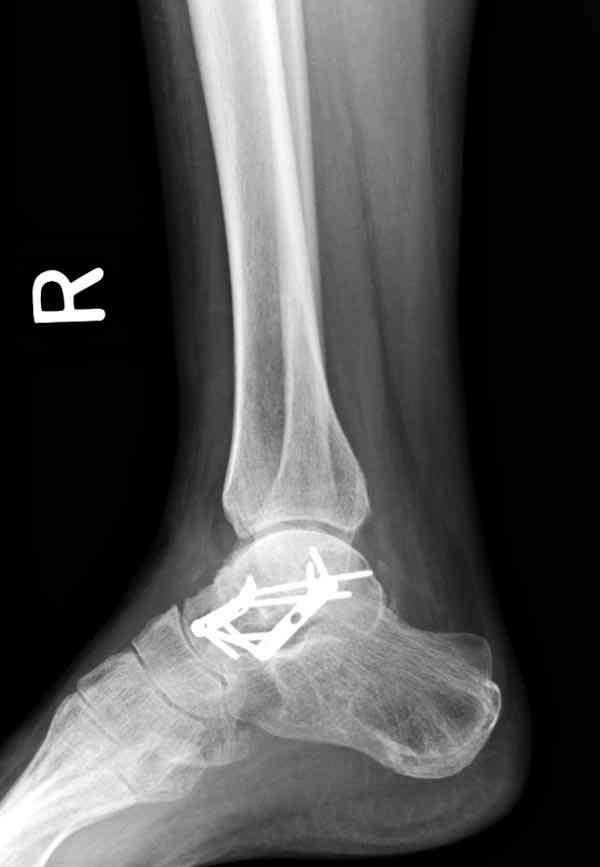

Случай с множественным оскольчатым переломом тарана оперированный из двойного доступа.

Через 2 мес.:

Через 8 мес.:

Через 14 мес.:

И второй случай из недавней ташкентской практики, (извините за качество ренгенограммы и только в одной проекции) случай падения с высоты (кстати моего друга - известного киноактера) - открытый

смещенный перелом тарана, с переломом переднего края дистального эпиметафиза большеберцовой кости.

При поступлении в приемной сделана первичная обработка с ушиванием открытой латеральной раны и вытяжением за пятку.

Из-за отсутствия времени пришлось оперировать на второе утро, из материала, что имеем на месте, фиксирован двумя шурупами, а третий-это контур сломанного жойстика в 4 мм. На дистальный медиальный конец тибиа antiglide 3.5 мм пластина. Через пару дней выписан и несмотря на предупреждение, самостоятельно начал нагрузку в 4 недели, время не ждет, снимается в боевике в Росийской Федерации.

Решили не связываться с остеосинтезом, а сделать сразу берцово-пяточный блок. Снимки в приложении.

По завершении удлинения, наверно, заштифтуем.

Комментарии/критика приветствуются.